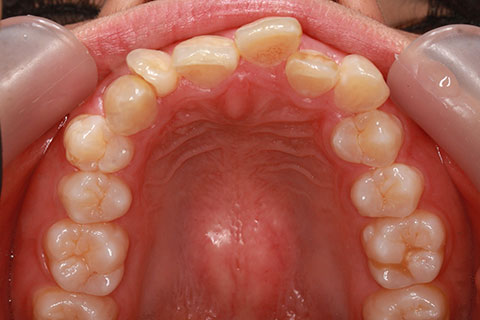

症例

治療前

治療後

- 年齢・性別

- 30歳女性

- 治療期間

- 3年0ヶ月

- 抜歯

- 上下左右4番抜歯

- 治療費

- 110万円

- 備考

- マルチブラケットを用いた矯正治療

- 治療内容

- 上下顎前突を4本抜歯にて矯正治療

- 施術の副作用(リスク)

- 表側矯正と比較して、歯根の角度を確立する「トルク」の力がかかりにくい。